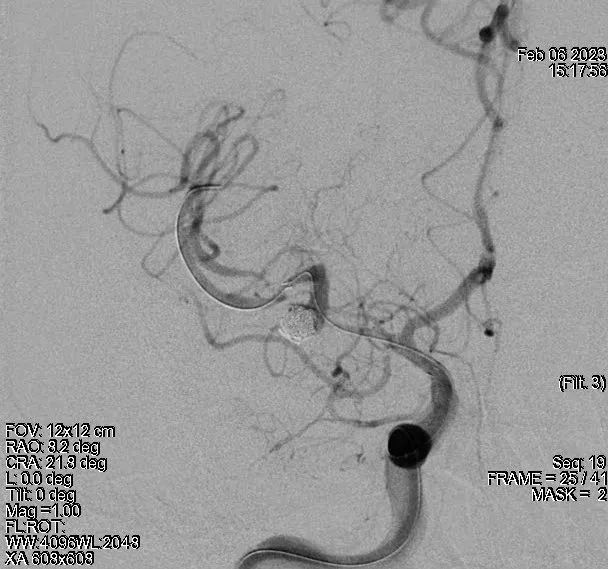

术前影像学资料(DSA)

治疗过程

血管成形

Angioplasty Balloon (2.0mm)

Postprocedural ICA Angiogram

支架辅助动脉瘤栓塞

再次血管成形

300-cm exchange micro-guidewire (0.014 inch)

Angioplasty Balloon (3.0mm)

治疗结果

术后3月DSA

术后18月DSA

1.特色:优先扩张狭窄血管,为微导管进入瘤腔提供条件;处理完动脉瘤后再次使用较大球囊扩张狭窄血管预防再狭窄;

2.可行性:术前完善高分辨磁共振、DSA以及血流动力学,结合患者病情制定合理手术策略;

3.安全性:术前经血流动力学与形态学充分评估动脉瘤应力情况与破裂风险,结合患者病情综合考量选择同期治疗狭窄与动脉瘤;

4.注意事项:术中扩张狭窄血管需谨慎加压,避免血流动力学改变致动脉瘤破裂出血。

6.术中扩张狭窄血管需谨慎操作,做到亚满意扩张,及时造影关注血流动力学改变情况。